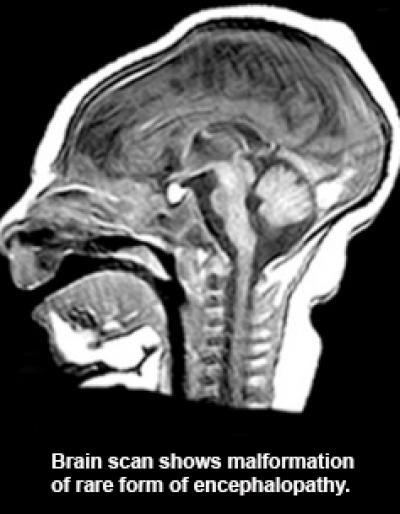

This brain scan shows malformation in a rare form of encephalopathy.

(Photo Credit: Duke Medicine)